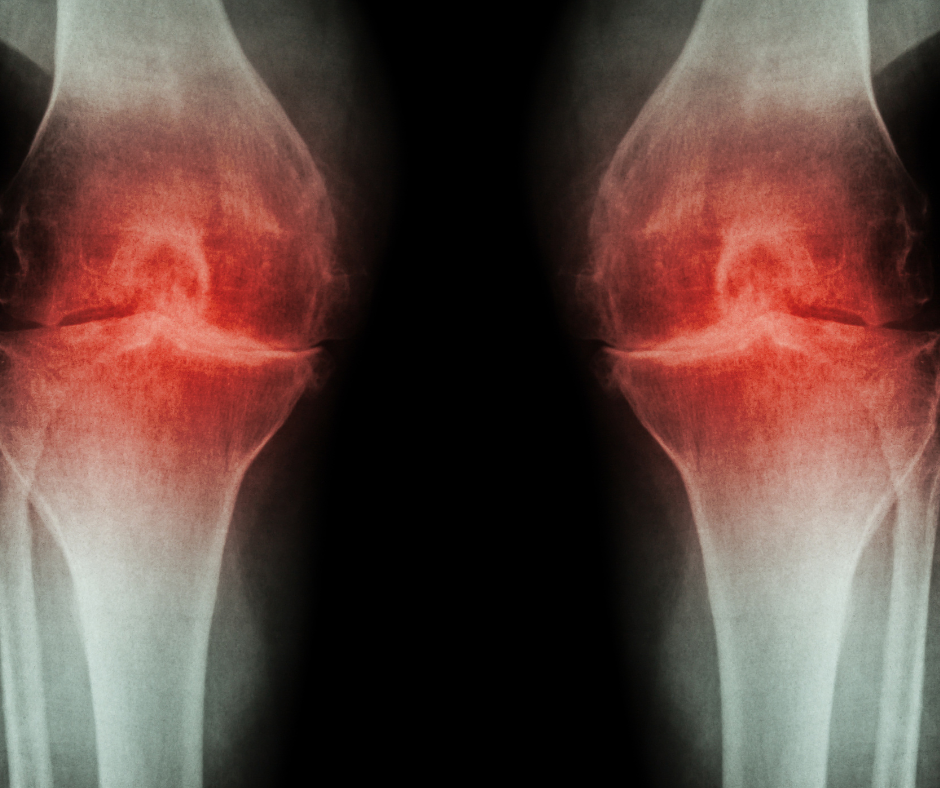

Une alimentation équilibrée et saine est essentielle pour réduire l’inflammation et préserver la santé articulaire. Certains aliments peuvent aider à soulager la douleur et à renforcer les articulations, tandis que d’autres peuvent aggraver la situation en augmentant l’inflammation et en favorisant la dégradation du cartilage. Si vous souffrez d’arthrose ou si vous souhaitez prévenir son développement, il est crucial de comprendre quels aliments éviter.

Dans cet article, nous allons explorer les 5 aliments à bannir de votre alimentation pour ne pas aggraver les symptômes de l’arthrose. Ces aliments, souvent considérés comme courants ou même « indispensables », peuvent en réalité causer des ravages sur vos articulations, ralentir la guérison et favoriser l’inflammation. Découvrez comment ajuster votre régime alimentaire et prendre des mesures concrètes pour améliorer votre qualité de vie tout en limitant les effets de l’arthrose.

L’arthrose est une maladie dégénérative qui nécessite une prise en charge à la fois médicale et préventive. Si les traitements traditionnels peuvent soulager la douleur, l’adoption d’une alimentation saine joue un rôle clé dans la gestion des symptômes et la préservation de la mobilité des articulations.

En évitant les aliments inflammatoires comme les sucres raffinés, les graisses saturées et trans, les produits laitiers, le glutamate monosodique et l’alcool, vous pouvez non seulement réduire l’inflammation dans vos articulations, mais aussi ralentir la progression de la maladie et améliorer votre qualité de vie.

Adopter une alimentation riche en aliments anti-inflammatoires, tels que les fruits, les légumes, les poissons gras, les noix et les graines, peut soutenir votre corps dans sa lutte contre l’arthrose. N’oubliez pas que chaque petit changement alimentaire compte et qu’il est possible de gérer cette condition de manière proactive pour maintenir une vie active et sans douleur.